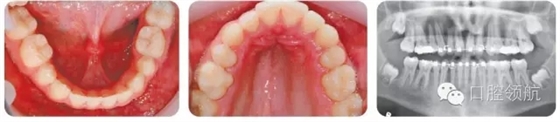

14歲男性患者,安氏I類咬合關(guān)系,輕度骨性II類長面型,嚴(yán)重的上牙列擁擠,上尖牙唇側(cè)錯位,雙側(cè)后牙反,前牙淺覆牙合(圖3.13)。